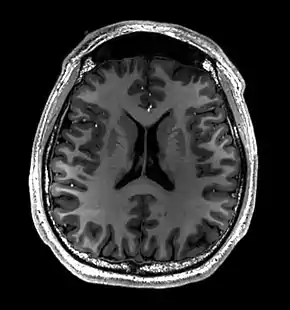

Magnetic resonance imaging of the brain

Magnetic resonance imaging of the brain uses magnetic resonance imaging (MRI) to produce high quality two-dimensional or three-dimensional images of the brain and brainstem as well as the cerebellum without the use of ionizing radiation (X-rays) or radioactive tracers.

- T1-weighted (T1W) images: Cerebrospinal fluid is dark. T1-weighted images are useful for visualizing normal anatomy.

Brain regions on T1 MRI

T1 (note CSF is dark) with contrast (arrow pointing to meningioma of the falx)